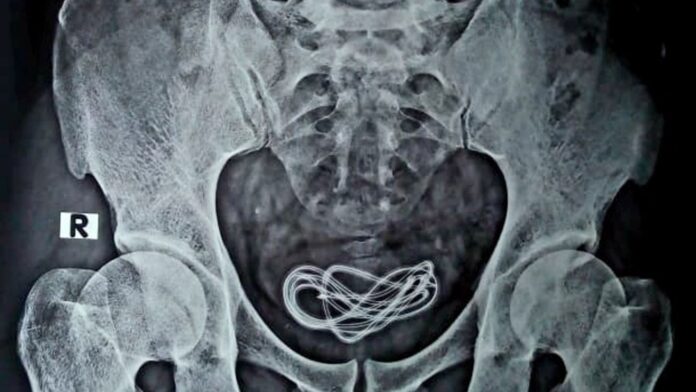

മൂത്രനാളിയിൽ ഇലക്ട്രിക്ക് വയർ കുത്തിക്കയറ്റിയ ഇരുപത്തഞ്ചുകാരൻ ആശുപത്രിയിൽ, വളരെ വിചിത്രമായ ഒരു വാർത്തയാണ് തിരുവനന്തപുരത്തുനിന്ന് പുറത്തുവരുന്നത്. മൂത്രനാളിയിൽ മൂന്നു മീറ്ററോളം നീളമുള്ള ഇലക്ട്രിക്ക് ഇൻസുലേഷൻ വയർ കുത്തിക്കയറ്റിയ ഇരുപത്തഞ്ചുകാരൻ ആശുപത്രിയിൽ. തിരുവനന്തപുരം മെഡിക്കൽ കോളേജ് ആശുപത്രിയിൽ രണ്ടര മണിക്കൂറോളം നീണ്ട ശസ്ത്രക്രീയയ്ക്ക് ഒടുവിലാണ് ഇൻസുലേഷൻ വയർ പുറത്തെടുത്ത് യുവാവിന്റെ ജീവൻ രക്ഷിക്കാനായത്. ഇലക്ട്രിക് വയർ യുവാവ് സ്വയം കുത്തിക്കയറ്റുകയായിരുന്നു. അപൂർവ്വ ശസ്ത്രക്രീയയ്ക്ക് ഒടുവിൽ പല കഷണങ്ങളായി മുറിച്ചാണ് യുറോളജി വിഭാഗം ഇലക്ട്രിക് വയർ പുറത്തെടുത്തത്. എന്തിനാണ് ഇയാൾ ഇത്തരമൊരു പ്രവൃത്തി ചെയ്തതെന്ന് വ്യക്തമല്ല. യുവാവിന്റെ ജീവൻ രക്ഷിച്ച ആരോഗ്യ പ്രവർത്തകരെ മന്ത്രി വീണാ ജോർജ്ജ് അഭിനന്ദിച്ചു.